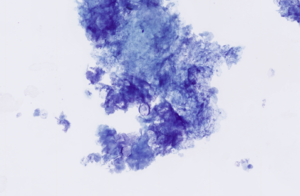

Cystic and keratinising lesions—including non‑neoplastic cysts—may yield only keratinaceous debris with scant or absent epithelial cells (Figure 14).

Figure 14 – Cytological features of keratinaceous debris from an epidermal cyst. The smear shows abundant anucleate keratin squames admixed with amorphous keratinous material. Modified Wright’s stain, ×40 objective.